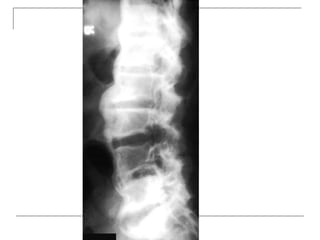

Plain radiograph

 AP

-loss of lumbar lordosis

-reduced disc space

-osteophytes

-deformity

-fracture (increase interpedicular distance)

-osteoporosis

-pedicle disruption

 Lateral

-fracture/wedging

-kyphosis

-spondylolisthesis